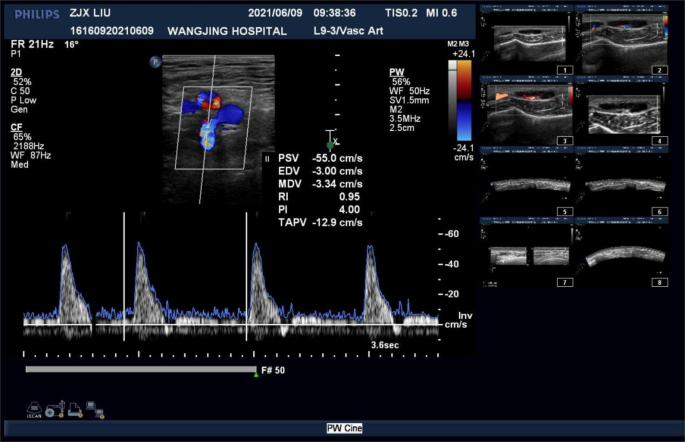

To provide a visual understanding of the ultrasound evaluation process, we have included a schematic diagram of the ultrasonic display interface used in this study (Fig. 1). This diagram shows the ultrasound record of a patient, highlighting the real-time blood flow velocity waveforms and the measured parameters, including PSV, RI, and PI, which are critical for our analysis.

Equipment: Philips IU 22 Color Doppler Ultrasound diagnostic system is used. Linear array probes: L9-3, L12-5 (the latter has a higher frequency and is suitable for slimmer individuals).

Examination Method: The examinee is positioned supine with the limb to be examined slightly abducted and externally rotated, toes pointing upwards. Using the 9L linear array probe, the examination involves scanning along the course of the femoral artery from the midpoint of the inguinal fold downwards, successively examining the femoral artery, deep femoral artery, and superficial femoral artery. The probe is placed transversely just below the inguinal ligament, slightly angled upwards, displaying the medial circumflex femoral artery with its transverse and ascending branches. The transverse branch runs between the adductor longus and adductor brevis muscles, while the ascending branch travels upward between the obturator externus and adductor brevis muscles. The deep branch proceeds deeply through the space between the pectineus, adductor longus, and iliopsoas muscles. Doppler ultrasound sample volume is placed at the center of the lumen of the medial circumflex femoral artery, at an angle less than 60° to the direction of blood flow, clearly displaying arterial blood flow for 3–4 cardiac cycles. The internal diameter (D) of the medial circumflex femoral artery is measured manually, and blood flow parameters such as peak systolic velocity (PSV), resistance index (RI), and pulsatility index (PI) are measured automatically by the computer system. Measurements are taken three times consecutively, and the average value is recorded.